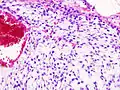

| Histopathologic image of chondrosarcoma of the chest wall. Surgical resection of recurrent mass. H & E stain. | |